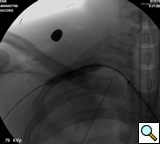

transected artery visualizing the pseudoaneurysm (Figure 2). A Viabahn covered stent (W.L. Gore & Associates, Flagstaff, AZ) is chosen for the appropriate size of the native vessel being careful not to oversize the stent graft. The stent graft is advanced across the lesion. Selective angiograms through the sheath may be performed to choose correct placement and appropriate landing zones. The stent graft is deployed under fluoroscopic visualization. Next, we utilize an appropriate sized 10 mm low pressure balloon to “iron out the edges” of the stent and bring it up to profile of the artery (Figure 3). Next, completion angiograms are performed to rule out endoleak and complete exclusion of the pseudoaneurysm, as well as to confirm distal runoff to the forearm and palmar branches of the extremity (Figure 4).